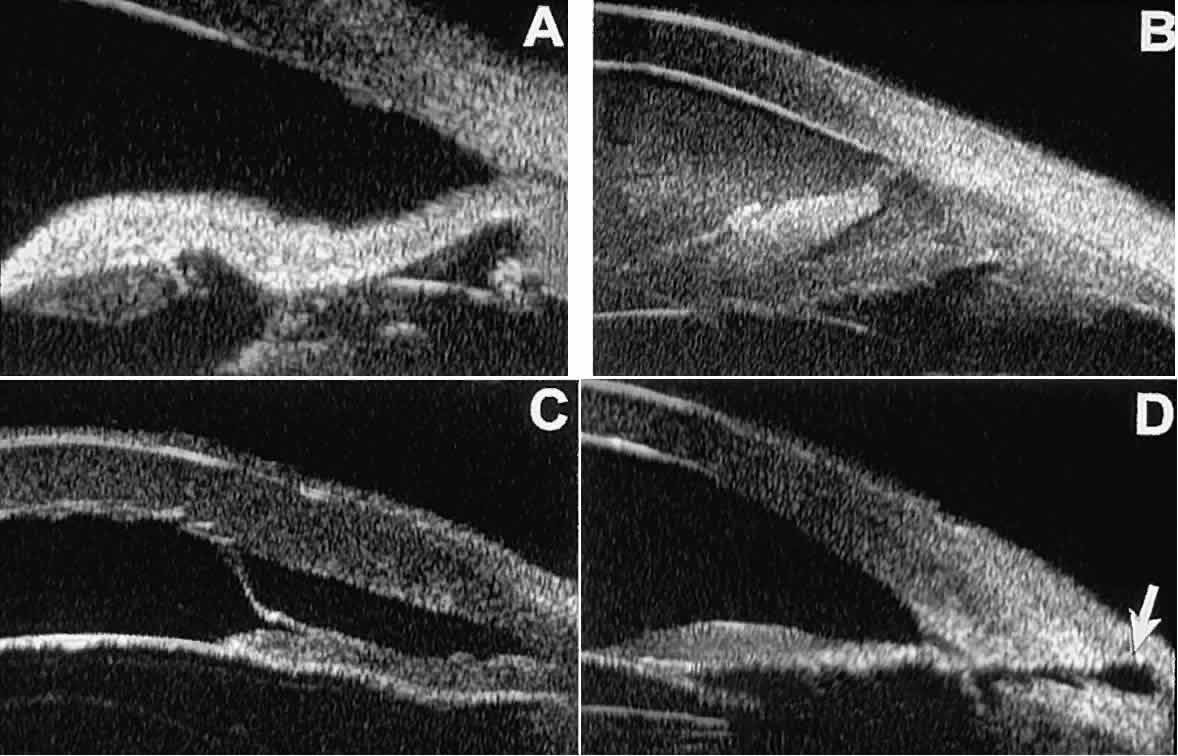

Cystic lesions of the iris and ciliary body can be of four types: primary neuroepithelial cysts, stratified squamous epithelial cysts, neuroepithelial cysts associated with solid tumors, and intratumoral cavities.15 Primary neuroepithelial cysts (see Fig. 22) are very distinct on UBM imaging. These lesions consist of a central sonolucent cavity surrounded by a thin wall of highly reflective neuroepithelial cells. They arise from the posterior surface of the iris (see Fig. 22A), in the iridociliary sulcus (see Fig. 22B and C), or from the inner aspect of the ciliary body (see Fig. 22D). They are often multifocal (see Fig. 22C and D) and bilateral.15 The largest lesions of this type typically occur in or near the horizontal meridians.

Stratified squamous epithelial cysts (Fig. 23) are almost exclusively unilateral and unifocal,15 have substantially thicker walls than do primary neuroepithelial cysts, and usually contain prominent intracavitary particles (desquamated epithelial cells). Almost all such cysts involve the peripheral iris and angle region. Such cysts are usually secondary to prior ocular surgery or laceration in which conjunctival epithelial cells were implanted into the iris stroma.

Fig. 23. UBM features of stratified squamous epithelial cysts of iris. A. Thick-walled implantation cyst of stratified squamous epithelium replacing normal iris. Note intracavitary particles. B. Bilobed stratified squamous epithelial inclusion cyst of iris with prominent intracavitary particles.

Secondary neuroepithelial cysts occur rather frequently in association with solid tumors of the iris or ciliary body.15 On UBM (Fig. 24), such cysts appear quite similar to the primary neuroepithelial cysts described above; however, they are associated with a solid mass arising within the iris or ciliary body.

Fig. 24. UBM appearance of neuroepithelial cysts associated with solid tumors of the iris and ciliary body. A. Single neuroepithelial cyst associated with iris melanoma. B. Multiple neuroepithelial cysts associated with iridociliary melanoma.